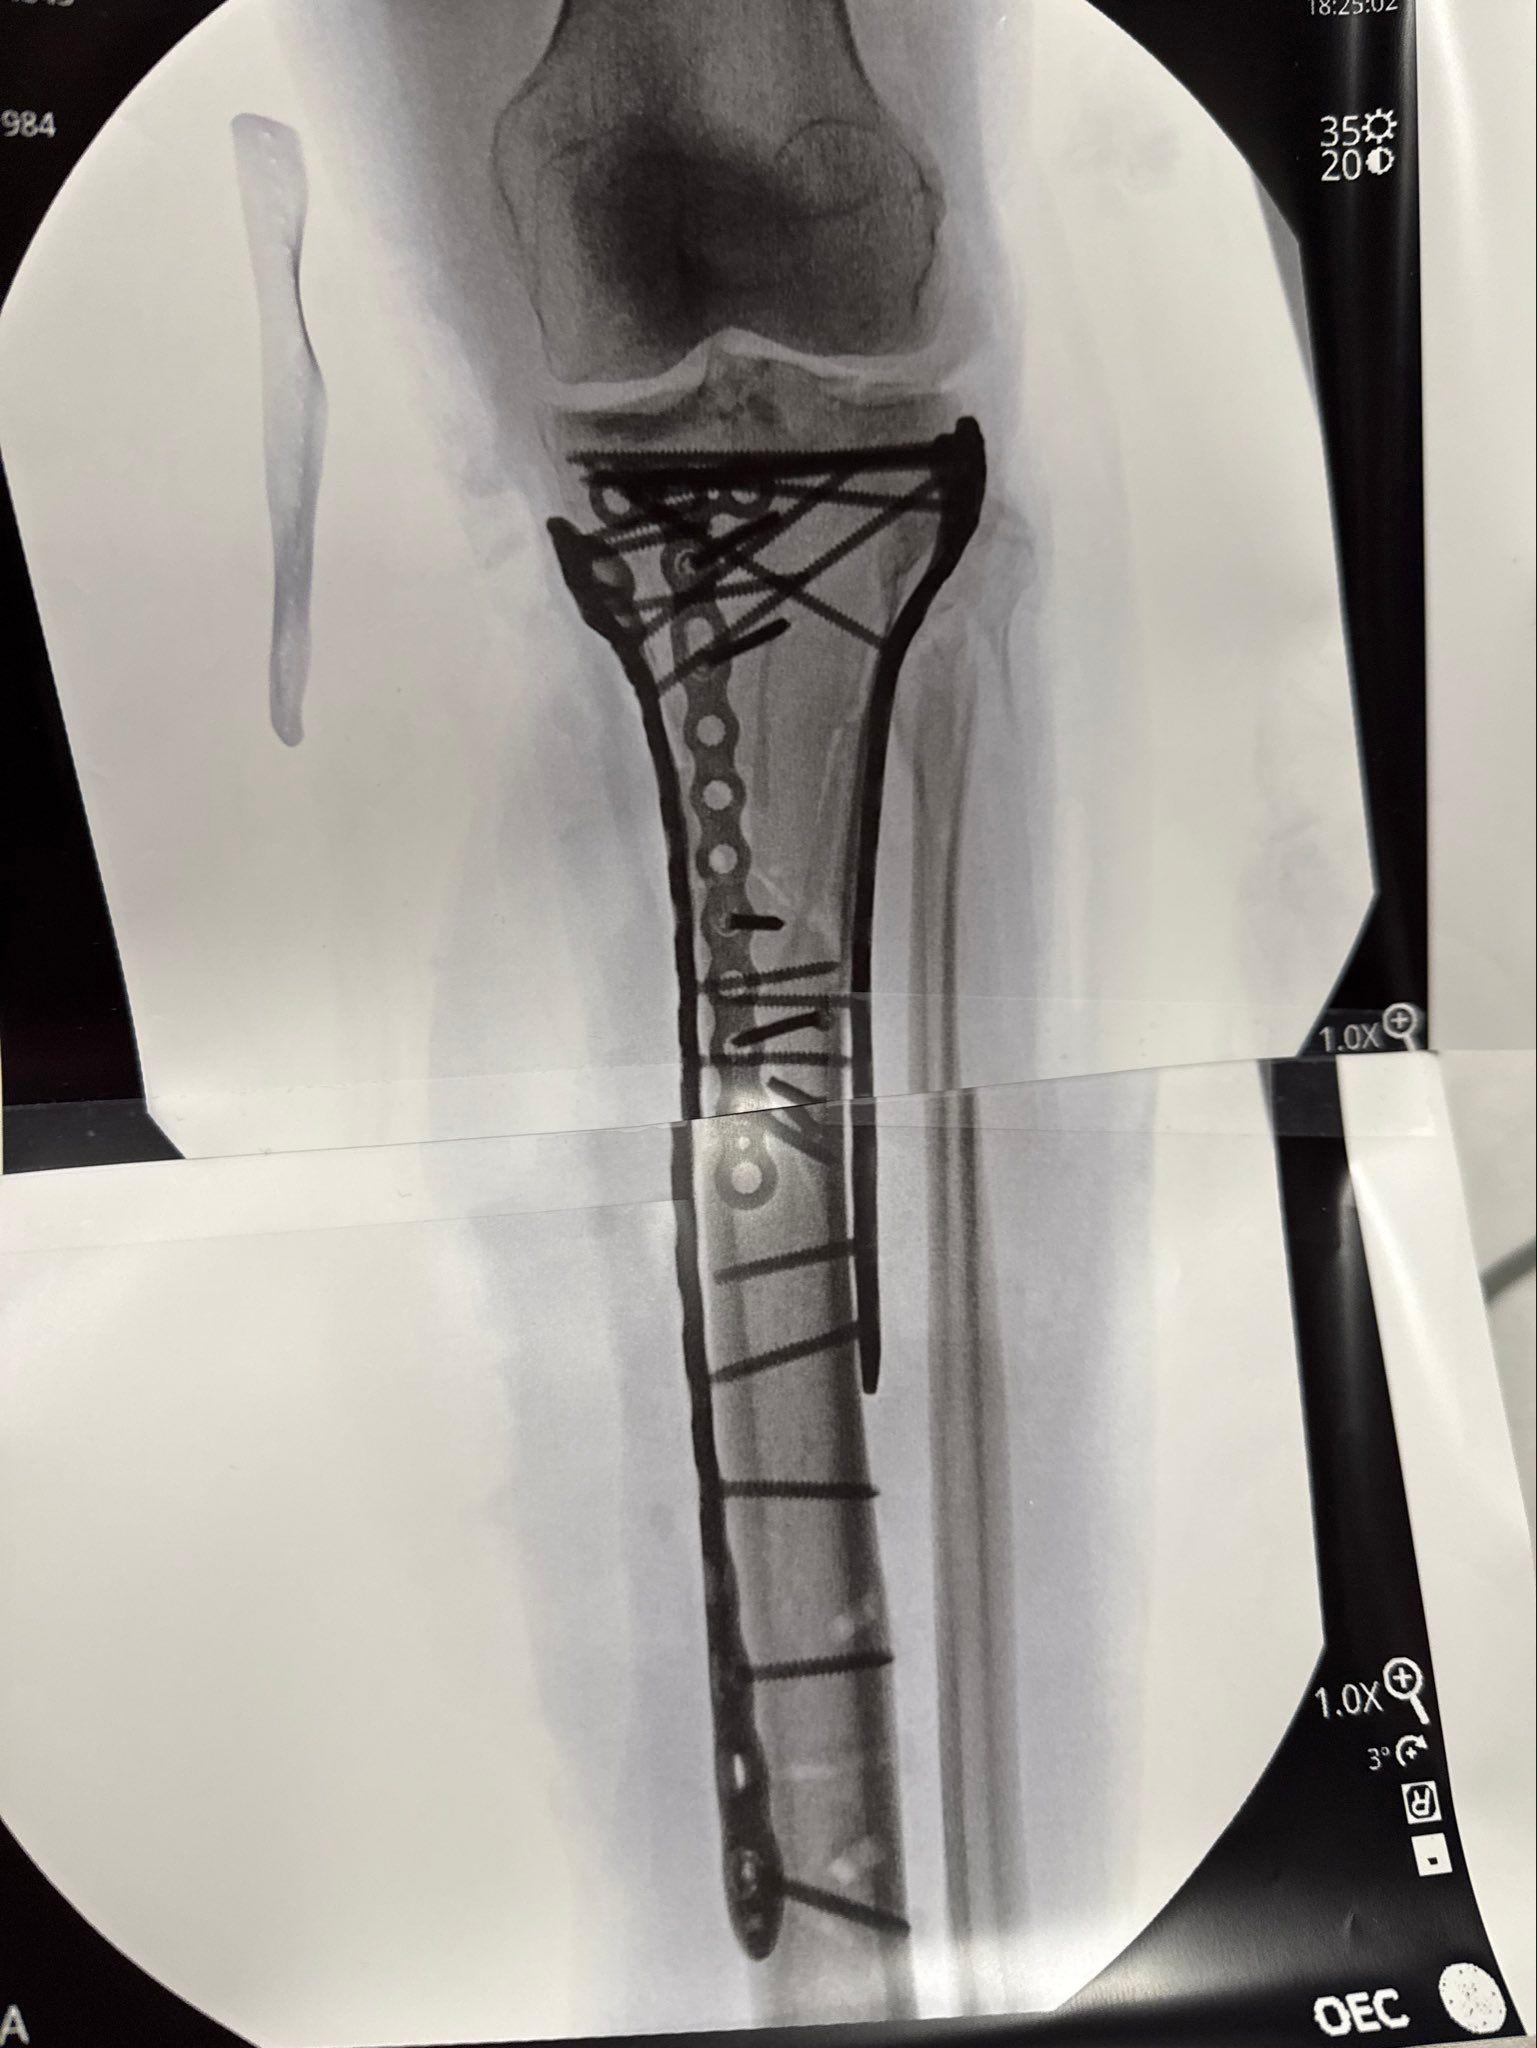

Lindsey Vonn/InstagramRendgenski snimak noge Lindzi Von posle više operacijaVon se takmičila na Olimpijskim igrama devet dana pošto je pokidala ligamente levog kolena.

Skijaška zvezda je imala šest operacija otkako je slomila nogu i skočni zglob u ženskom spustu u Italiji 8. februara.

Noga mi je bila „u komadima“, rekla je.

Imala sam sindrom kompartmenta, pritisak unutar mišića, koji ograničava protok krvi, a hirurg me je hitno operisao kako bi ublažio pritisak, dodala je.

„Dr Tom Haket mi je spasao nogu – spasao ju je od amputacije.

„Otvorio je obe strane moje noge, tako da je bila otvorena i pustio je da diše, takoreći. Spasio me je“, rekla je 41-godišnja skijašica.

„Onda ću odlučiti da li želim da izvadim sve metale iz noge ili ne, a onda ću ponovo na operaciju zbog prednjih ukrštenih ligamenata (ranije povrede, pre ZOI).“